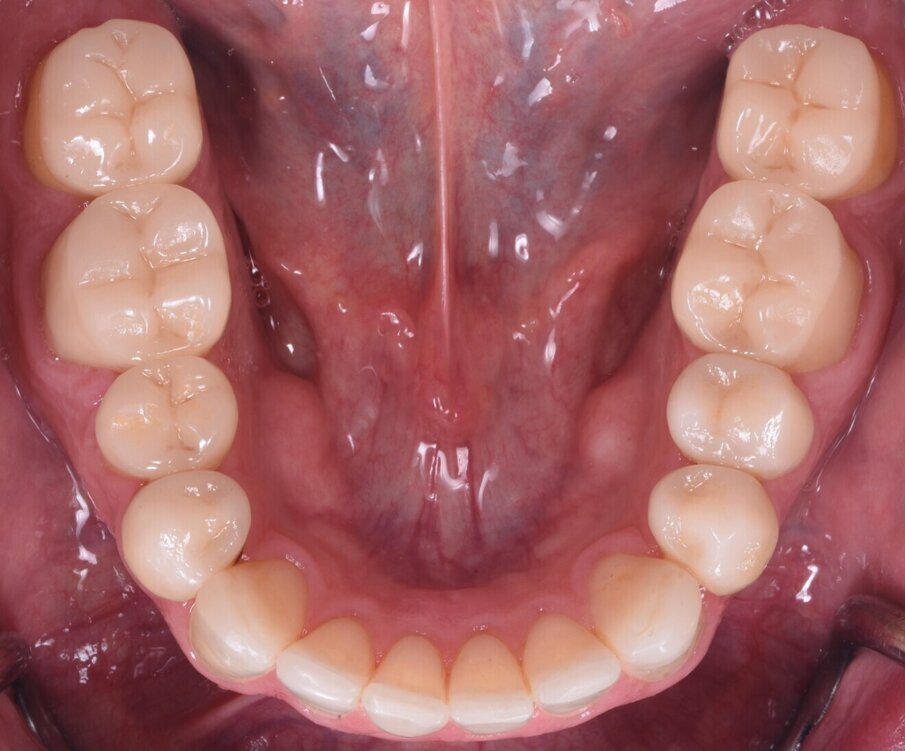

Nakonec byly finální korunkové náhrady (obr. 14) adhezivně fixovány v ústech za izolace kofferdamem (obr. 15). Pacient byl sledován několik týdnů po cementaci náhrad (obr. 16 a 17).

Obr. 17a–c: Finální intraorální fotografie.